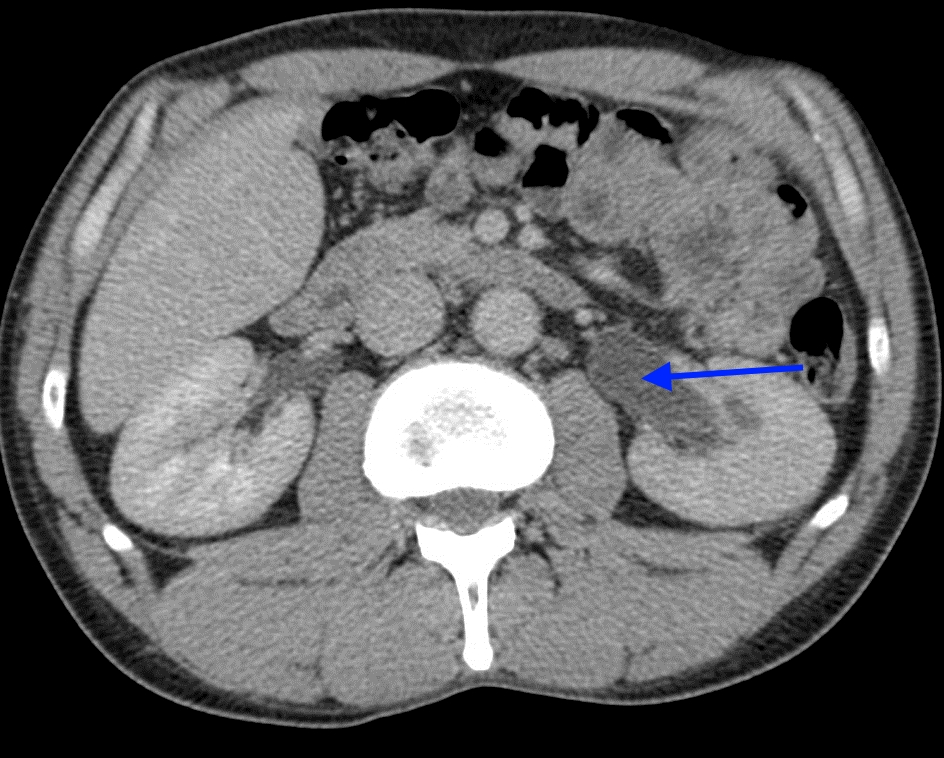

Изображения КТ конкрементов мочевого пузыря